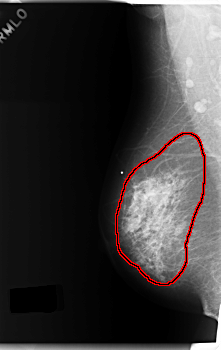

FILE: C_0179_1.RIGHT_MLO.OVERLAY

TOTAL_ABNORMALITIES 1

ABNORMALITY 1

LESION_TYPE CALCIFICATION TYPE PLEOMORPHIC DISTRIBUTION REGIONAL

LESION_TYPE MASS SHAPE IRREGULAR MARGINS ILL_DEFINED

ASSESSMENT 5

SUBTLETY 5

PATHOLOGY MALIGNANT

TOTAL_OUTLINES 1

BOUNDARY

C_0179_1.RIGHT_MLO

RIGHT_MLO LINES 5944 PIXELS_PER_LINE 3744 BITS_PER_PIXEL 12 RESOLUTION 50 OVERLAY